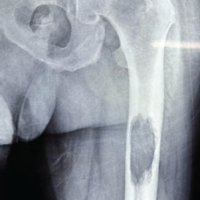

Eighty patients were taken in this study who had Humerus mid-shaft fractures. They were divided into two groups. In ABP group, only 1 case showed superficial infection, whereas in ORIF group,2 cases showed infective non-union. 2 cases of group-1 and 5 cases of group-2 had postoperative radial nerve palsy which all of them recovered spontaneously. Hence, the rate of palsy is more with ORIF group which is significant [p-value<0.5]. One case of ABP resulted in non-union whereas two cases of ORIF showed nonunion due to infection, out of which one case went through grafting and the other case was lost in follow-up (Table 1).We studied that the range of motion at shoulder joint is more with ABP group comparatively as the p-values are significant more with flexion, extension, abduction, internal rotation and external rotation. Out of 40 cases of ABP, 19 cases showed score34, 10 cases showed 33,10 cases-32,1case showed 30.Outof 40 case s ORIF, 10 cases showed 34, 7-33, 9-32, 2-28, 1-24, 1-22. Because of less soft tissue dissection, ABP shows good shoulder outcome (p-value<0.05) (Table-2).In ABP group, 24cases showed 100,1-98,1-975.InORIFgroup,21cases showed100,15-95,3-90,1-85. Hence, ABP shows better elbow outcome than ORIF cases (Table-3).ABP cases shows early radiological union comparatively{12weeks-mean} with p-value<0.05 (Table-4).The surgical time is more with ABP since it is a closed reduction method (Table-5). The mean number of c-arm shoots was 104.28 in Group-1 and 8.05 in group-2. There was no difference in the outcome when compared to age, sex, side or obesity.

Thakor et al. highlighted the construct’s ability to withstand biomechanical stresses through relative stability[12]. Hence in our analysis, ABP cases had radiological union by 12.75 weeks (mean)and ORIF cases had by 14.75 weeks (mean). Even though there is absolute stability in conventional method, ABP showed less time period of time. Yang’s comparison of MIPO and ORIF favoured ABP for its superior safety and functional outcomes [13], and Bhandra et al. confirmed its safety in straightforward fracture patterns when performed by experienced surgeons [14]. In our study, mean UCLA shoulder score was 33.15 in ABP and 31.53 in ORIF. The mean Mayo elbow score was 98.13 in ABP and 97 in ORIF. Therefore, the functional outcome is better in ABP group similarly to the previous studies. Anatomical safety remains paramount. Apivatthakakul et al. identified high-risk zones for nerve injury during screw placement, emphasizing the need for precise technique [15]. Suwannaphisit et al. further demonstrated the variability in radial nerve anatomy, underlining the importance of preoperative planning and intraoperative vigilance [16]. 5 cases of ORIF and 2 cases of ABP showed postop radial nerve palsy in our research. All of them recovered spontaneously. The reason to have radial nerve palsy in ABP is because not having knowledge about the precise location of radial nerve and it varies in each individual and may have anatomical anomalies, and uncontrolled drilling where the drill bit can hit the nerve posteriorly. ABP preserves periosteal blood supply, limits soft tissue disruption, and allows micromotion conducive to callus formation—all factors that support fracture healing and reduce complications such as infection and non-union. Although technically demanding, ABP with DCP represents a promising and practical alternative to traditional plating methods, especially when performed by skilled surgeons. This study is a reliable research as it covers a good sample in both groups with no sexual bias and the most common age group and followed the cases for the period of 1year. However, it doesn’t include the elderly population where DCP cannot be used, doesn’t include post-traumatic radial nerve palsy (GA-3C with wrist drop), as whether ABP does not involve radial nerve exploration or the need of exploration is a must, as most of them are conserved in all types of nerve injury except in transection. These are its limitations and a meta-analysis should be done, which can include all types of open fractures with and without radial nerve palsy or should be studied alone.